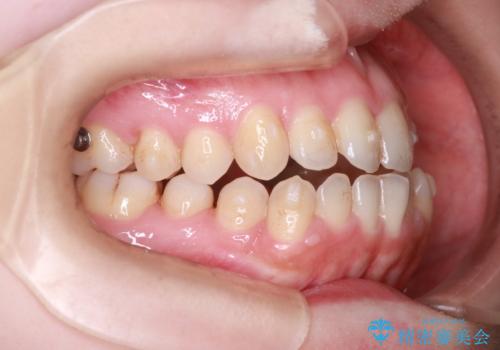

【オープンバイト】前歯のがたがたをなおしたい。

- 笑った時の前歯の見た目が気になることを主訴に来院されました。

上の歯が下の前歯を少し隠すぐらいを目指し、インビザラインにて治療を行いました。